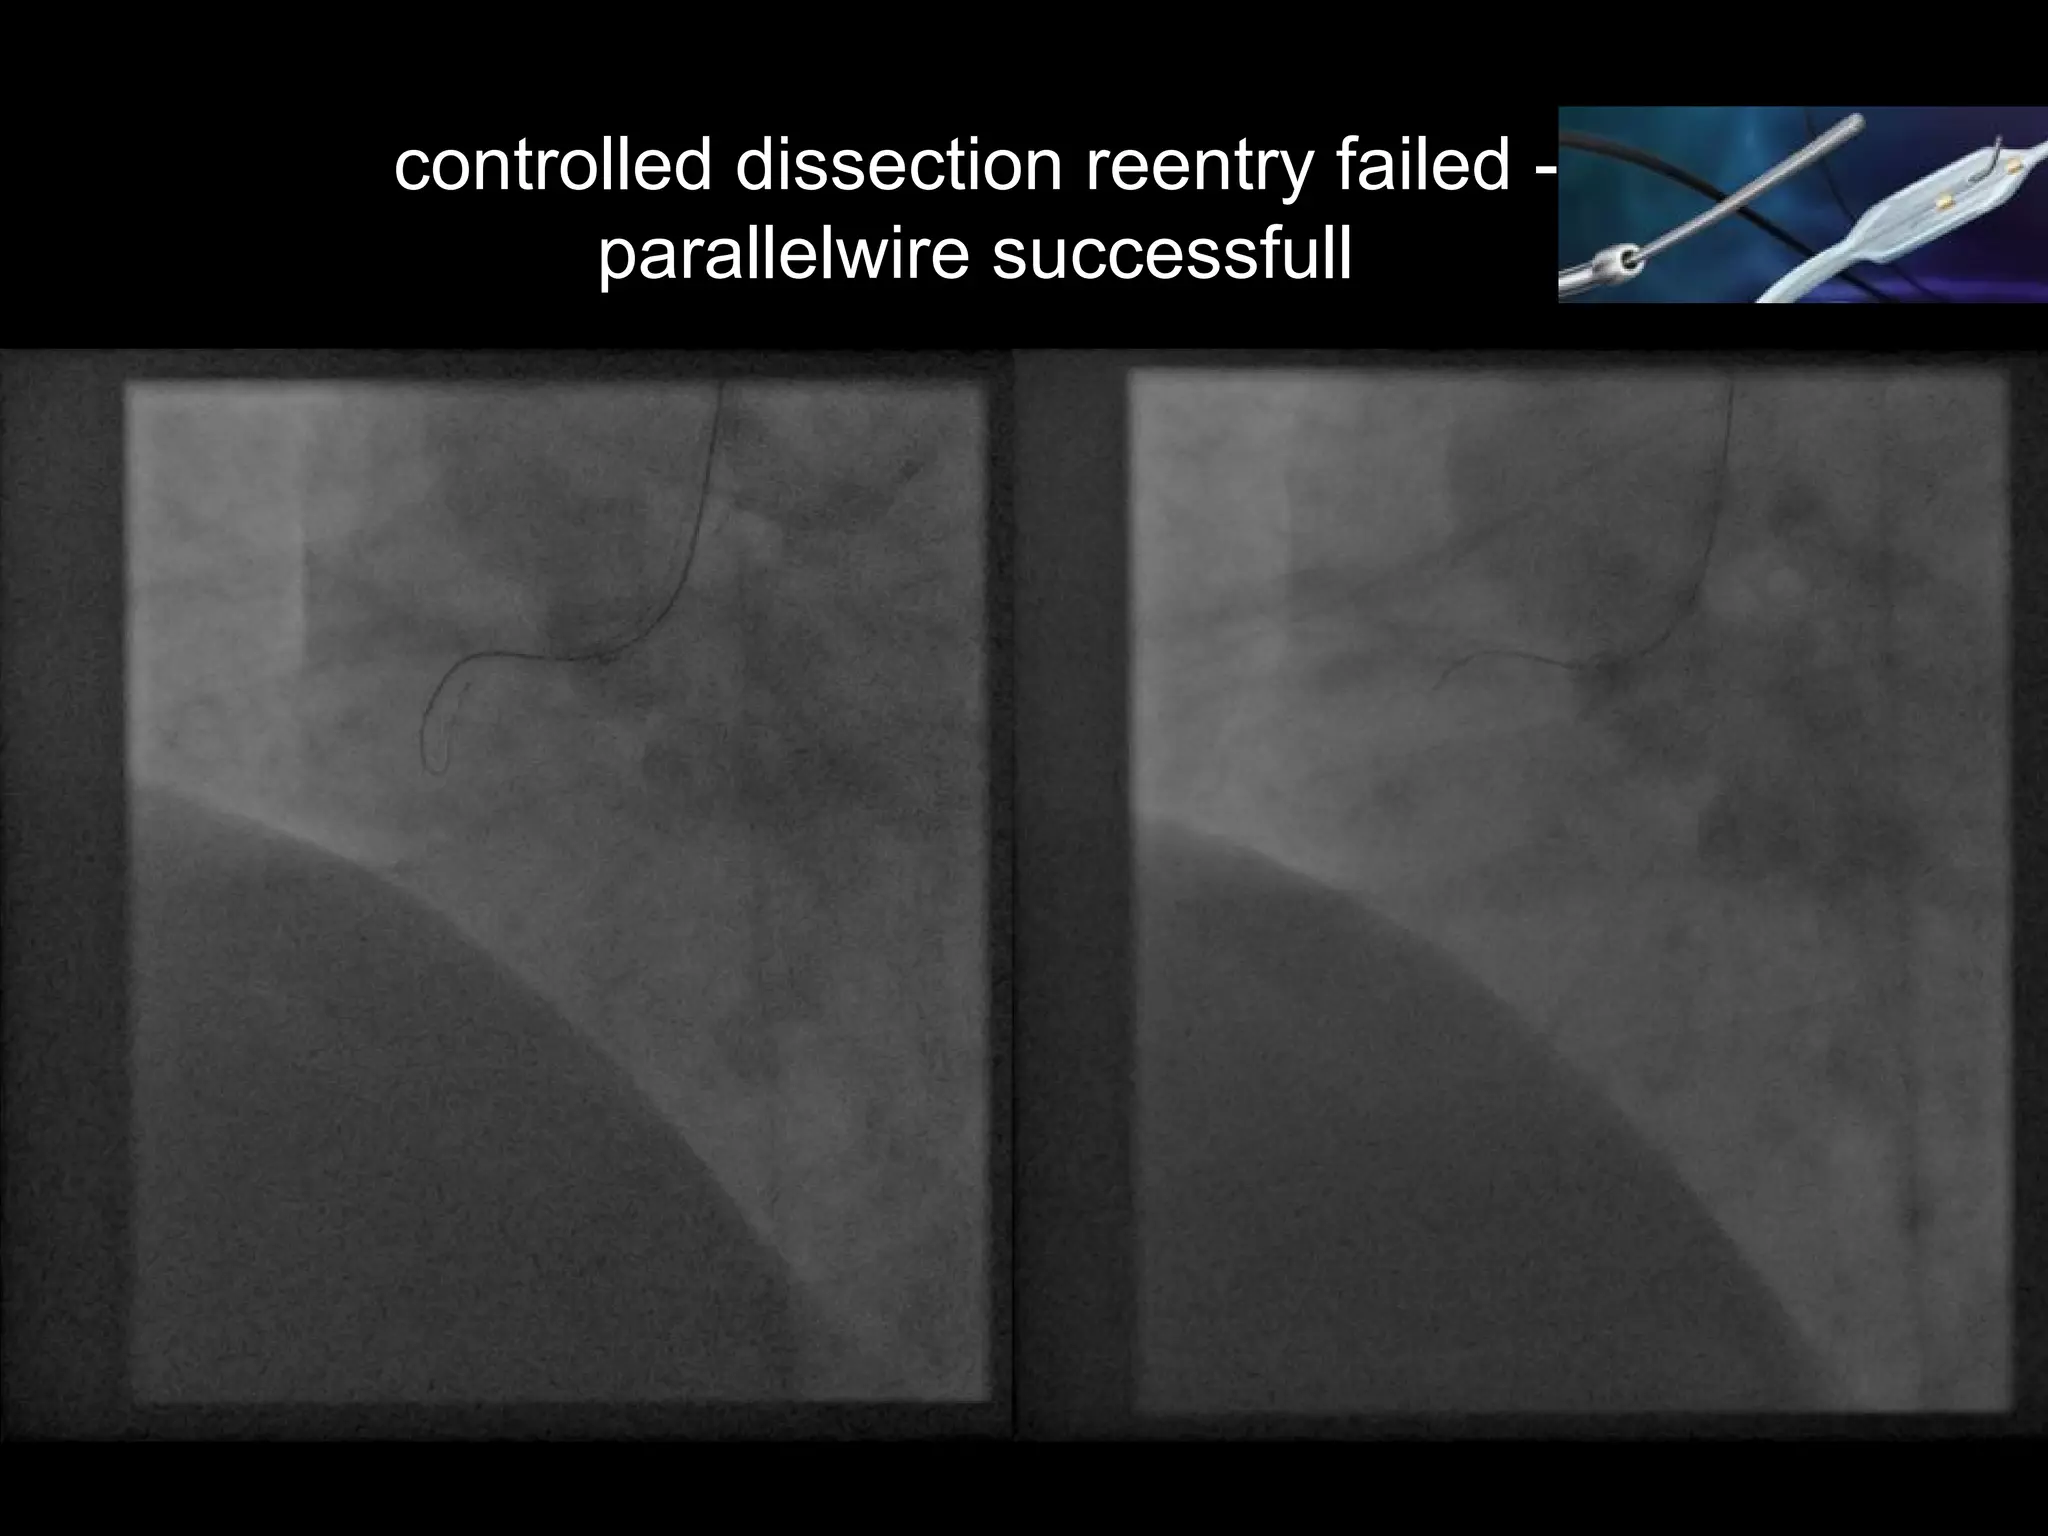

controlled dissection reentry failed -

parallelwire successfull